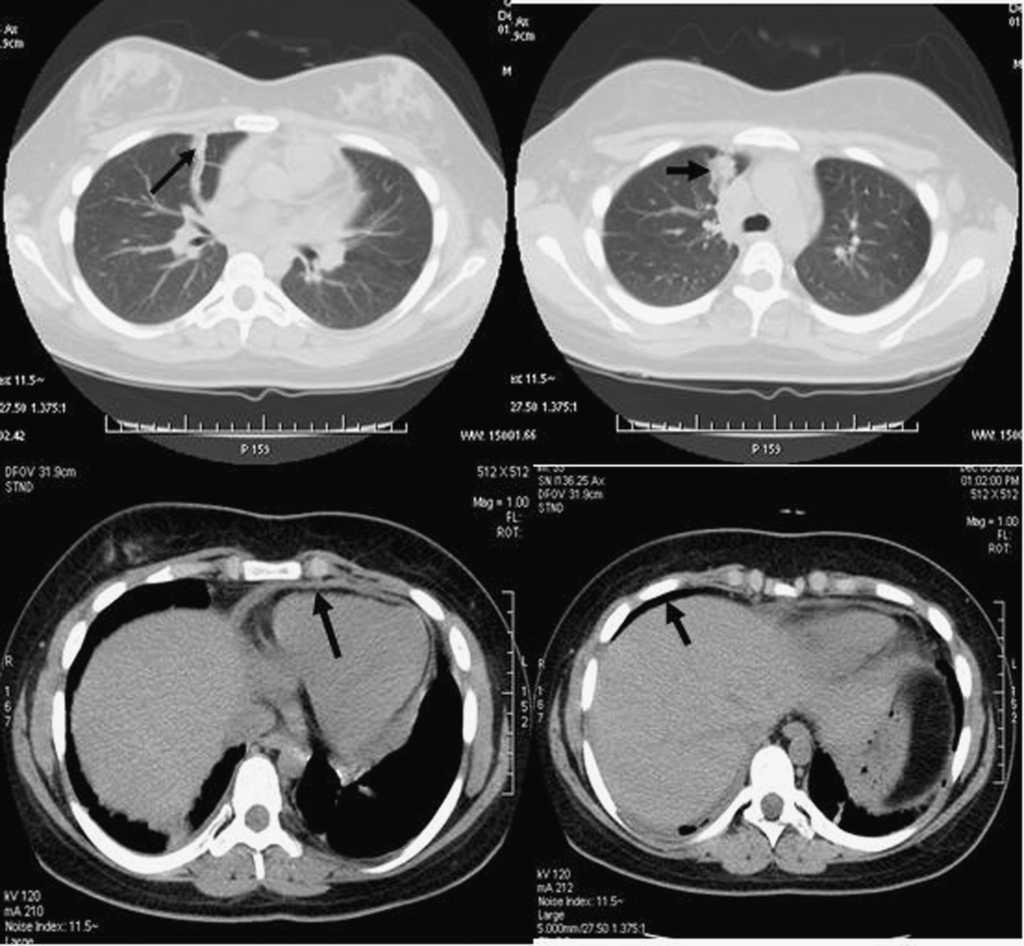

Diez meses después ingresa por importante distrés respiratorio con tiraje subcostal y supraesternal, taquipnea, tos, febrícula de 37,5 °C, saturación de oxígeno inferior al 90% y auscultación pulmonar con crepitantes aislados en las bases. El tratamiento en ese momento es de hidroxicloroquina, prednisona y metrotexato por vía oral. Las pruebas de laboratorio, incluida la proteína C reactiva, son normales; los anticuerpos antifosfolipídicos y el anticoagulante lúpico son negativos. El ecocardiograma es normal. La radiografía de tórax muestra una discreta reacción pleural subcostal bilateral, una afectación pulmonar intersticial y una ligera disminución del volumen pulmonar. La TC torácica muestra focos consolidativos y pequeñas atelectasias en ambos pulmones (con predominio derecho), y lámina de líquido pleural bilateral y de líquido pericárdico (fig. 1). En ese momento se pauta tratamiento antibiótico de amplio espectro y también se suspende el tratamiento con metrotexato por ser, junto con la ciclofosfamida, los fármacos que con más frecuencia se describen como causa de neumonitis inducida por fármacos9.

Figura 1. Imagen de la tomografía computarizada torácica realizada a la paciente durante su ingreso. Se observan de izquierda a derecha en sentido horario: atelectasia en campo pulmonar derecho, condensación en campo pulmonar derecho, fina lámina de líquido pericárdico y lámina de líquido pleural bilateral.